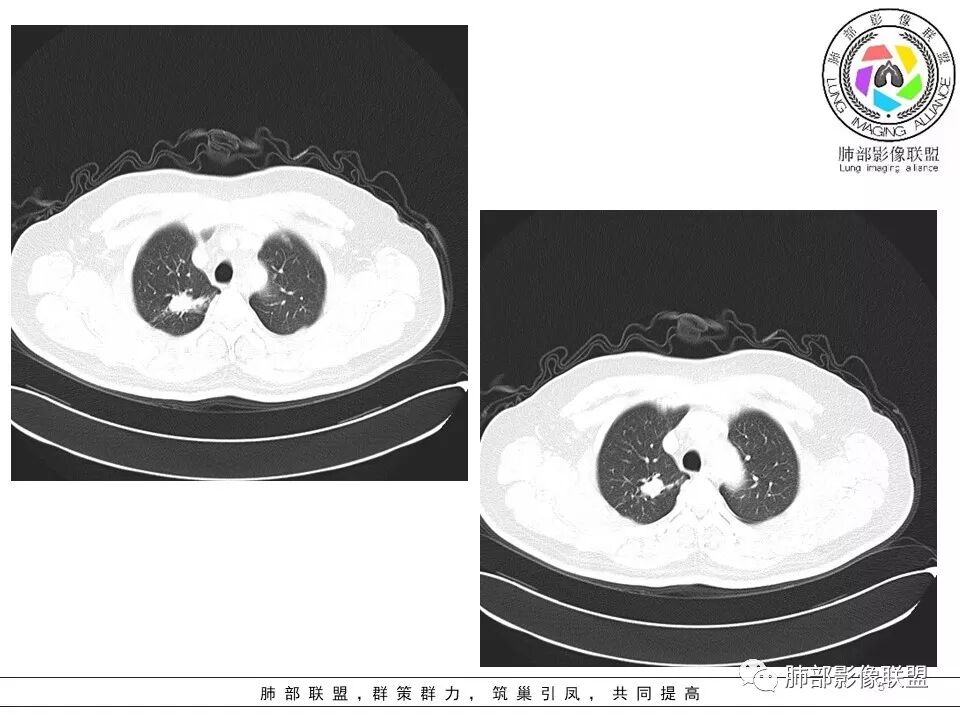

遗憾的是:层厚太厚,无重建

这些是否是边界清楚GGO?

因此我们需要的是:薄层、重建,看GGO边缘、看整体形态

瘢痕癌就需要薄层、重建观察更妥当

南边:瘢痕癌就需要薄层、重建观察更妥当

生来征服~浪子:部分层面彭隆的挺明显。

Coke with ice:瘢痕癌+1